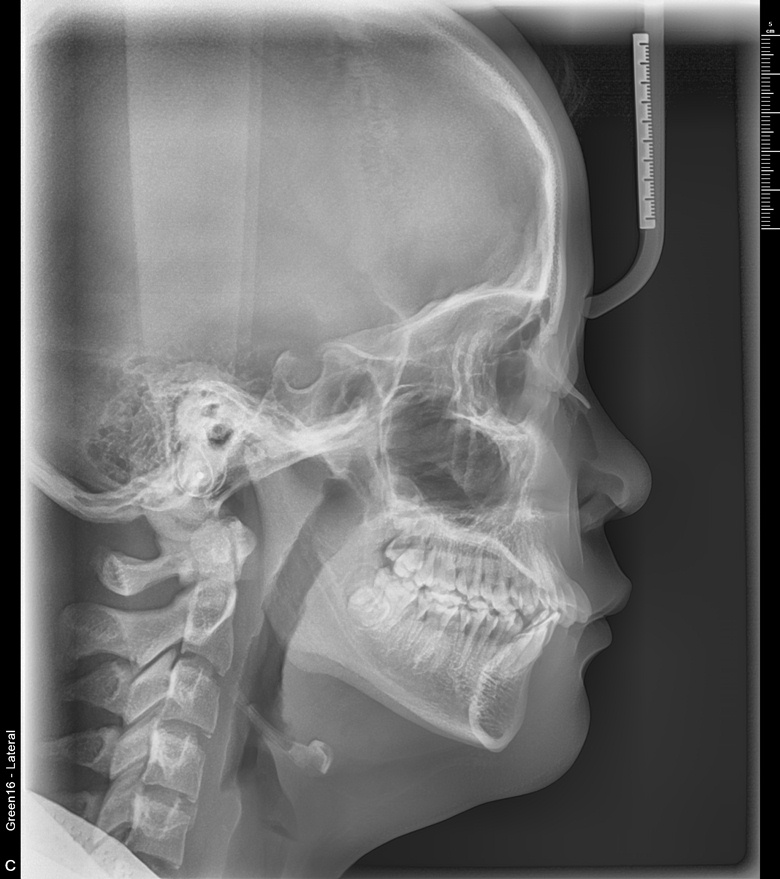

치료 후 사진입니다.